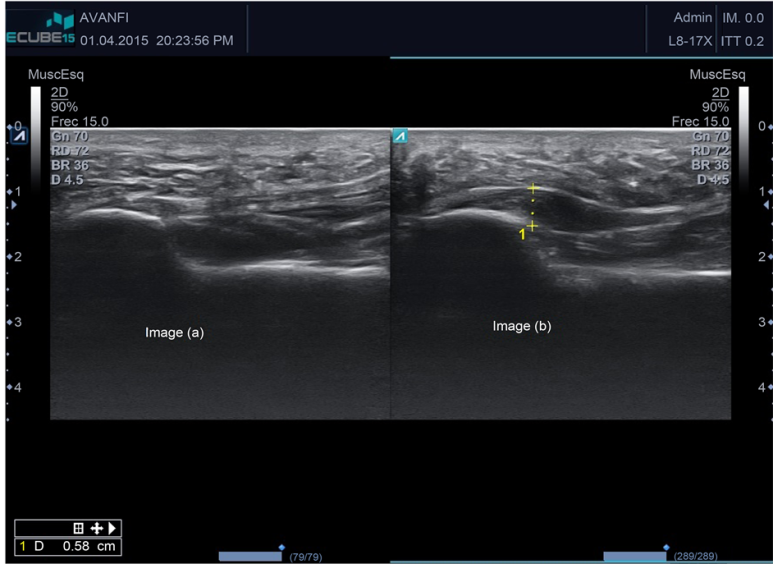

초음파와 MRI에서 근막의 정상두께는 3-4mm입니다.

그런데 염증이 생겨 퉁퉁 부으면 4mm이상 두꺼워집니다.

염증으로 주변 조직에 물이 차있기도 하고,

도플러상 혈류신호가 보이기도 합니다.

족저근막의 가장 두꺼운 부분을 측정해보니 무려 9mm가 나옵니다.

정상 3-4mm인데, 2배 이상 된 것이죠.

보통 족저근막염 환자들이 5mm 내외 인걸 감안하면 심각한 상태입니다.